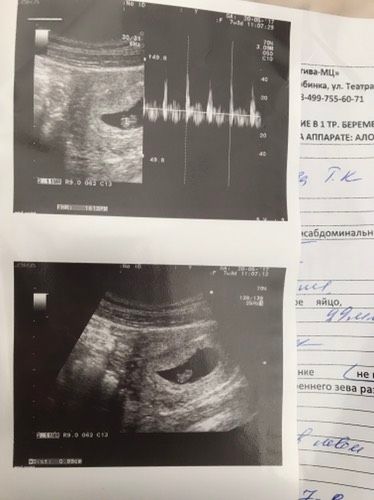

Мое первое узи, пошла на платное, не дотерпела до планового, и вот он! Мой маленький головастик! Сказали развитие в норме и все хорошо, сердечко бьется, плакала лежала, я так долго ждала мое счастье ( срок 7 недель 3 дня )

Нет, там посветили минутку, все без патологий и плюс я боялась внематочной, теперь я спокойна, мой кроха развивается как надо и где положено